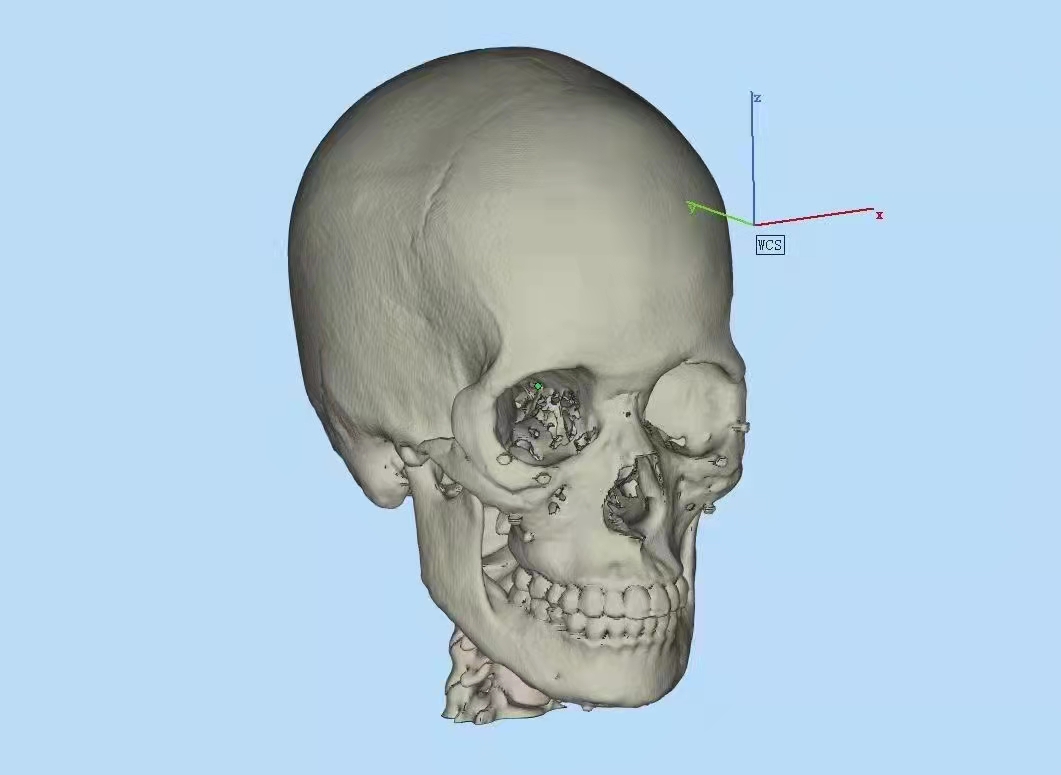

3D打印前需要准备好3D模型文件,对于教具,展览用的模型,可以自己建模,或者网上找,对于医疗用的,可以通过CT扫描的文件转化成打印用的软件格式,有了模型文件,就可以给打印服务工厂打印了。

上面就是3D打印后,经过初打磨的模型,能够精确复原模型文件,一般打印树脂模型,打印精度为0.1,颜色为白色,打印时间2天就可以了。